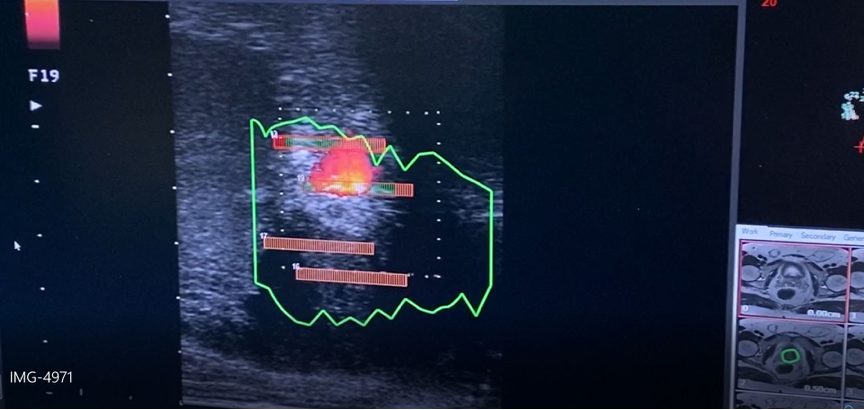

Με την ίνα του λέιζερ καταστρέφεται ο υπερπλαστικός ιστός του προστάτη, ενώ τις επόμενες ημέρες συνεχίζεται η καταστροφή δια μέσω της φυσιολογικής διαδικασίας που ονομάζεται πηκτική νέκρωση έτσι ώστε ακόμα μεγαλύτερη ποσότητα προστατικού ιστού να νεκρώνεται, επιτρέποντας την καλύτερη ούρηση.

Η εστιακή θεραπεία με φωτοεξάχνωση (laser)